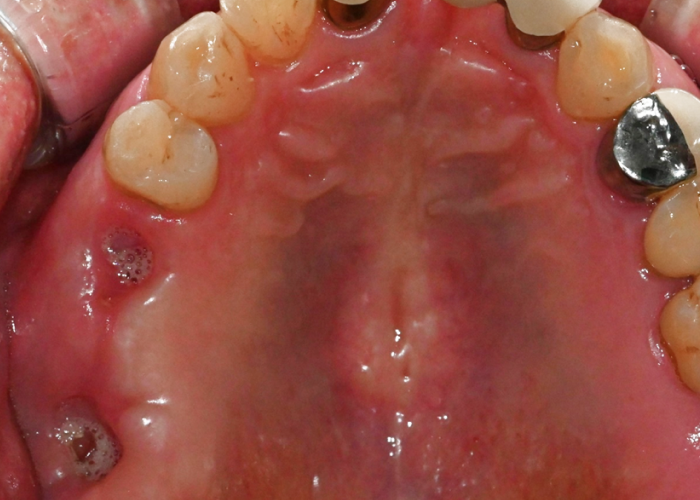

오른쪽 위 어금니를 발치한 환자분이

내원하셨습니다.

오래된 브릿지 보철물이 탈이 나면서

뿌리까지 손상된 상황이었고,

이미 어금니임플란트 경험도

있으셨습니다.

문제는

발치 직후라 잇몸과 뼈가

충분히 회복되지 않았다는 점이었습니다.

치아 흔적이 그대로 보이고,

뼈와 잇몸 모두 부족한 상태였죠.

발치 직후

어려운 조건이었지만,

울산 어금니임플란트를 단단하게 심어

안정적인 고정을 확보했습니다.

식립이 끝난 뒤에는 뚜껑을 씌워

잇몸이 차분히 회복될 수 있는 환경을

만들어줍니다.

이 잇몸이 단단히 자리 잡는 데에는

보통 약 4개월 정도의 시간이 필요합니다.

그 기간 동안 환자분께서는

당일에 제작된 임시 치아를 사용하시면서

일상생활을 이어가실 수 있습니다.